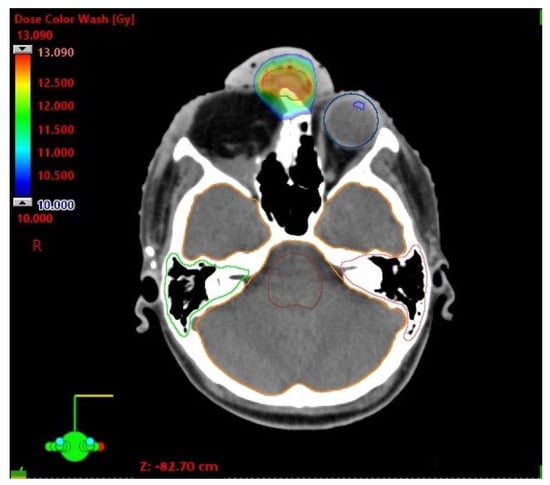

| D Max [Gy] | |

|---|---|

| Brainstem | 2.65 |

| Optic chiasm | 3.05 |

| Cochlea left | 0.95 |

| Cochlea right | 1.04 |

| Lens left | 0.22 |

| Eye left | 2.70 |

| Brain (ethmoid sinus region) | 9.00 |

| Optic nerve left | 2.26 |

| Spinal cord | 0.78 |